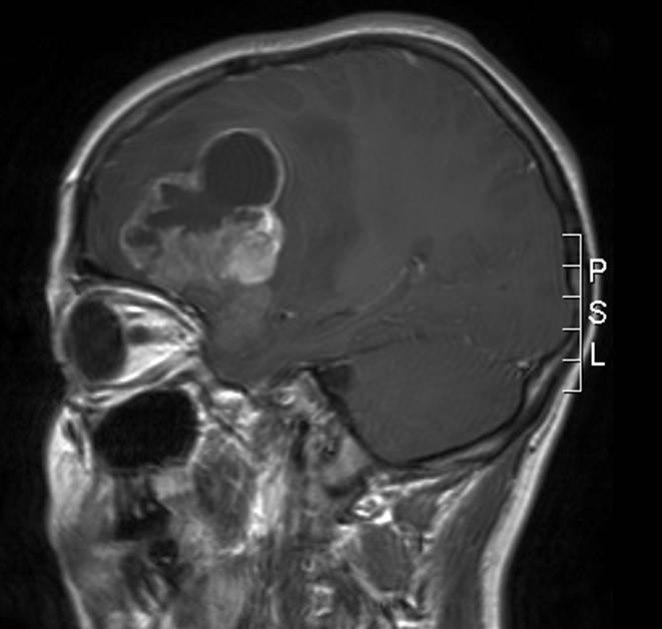

Anaplastisk ependymom, sagittalt snitt

Gjengitt med tillatelse av Radiologisk avdeling, Universitetssykehuset Nord-Norge